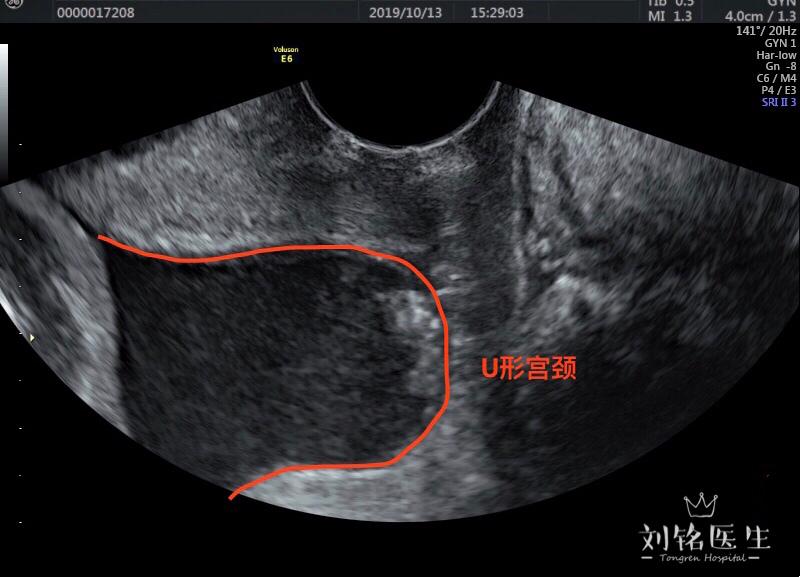

宫颈长短和流产早产是否有关

图片尺寸800x577

而没有生过孩子的女性她们的宫颈的形状是呈"0型"的,有经验的医生只要